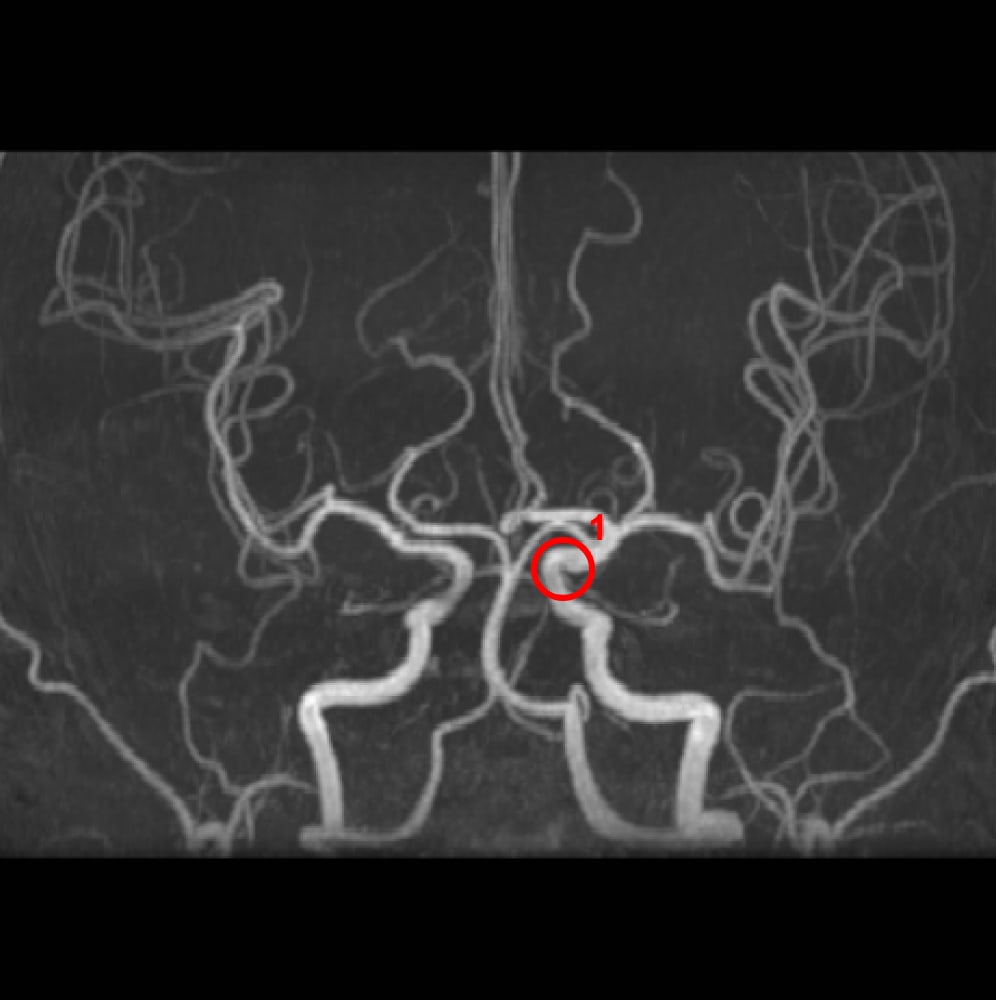

解析事例

内頚動脈-後交通動脈